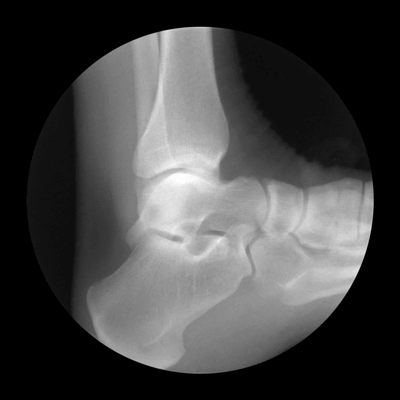

Биомеханика голеностопного сустава на рентгене

Голеностопный сустав образован сочленением дистального конца большеберцовой и малоберцовой кости с таранной костью. Движения стопы осуществляются одновременно в голеностопном суставе, подтаранном суставе и поперечном суставе предплюсны. За тыльное и подошвенное сгибание стопы отвечает в основном голеностопный сустав; за пронацию и супинацию стопы — подтаранный сустав (рис. 2.1), а отведение и приведение стопы происходит в поперечном суставе предплюсны.